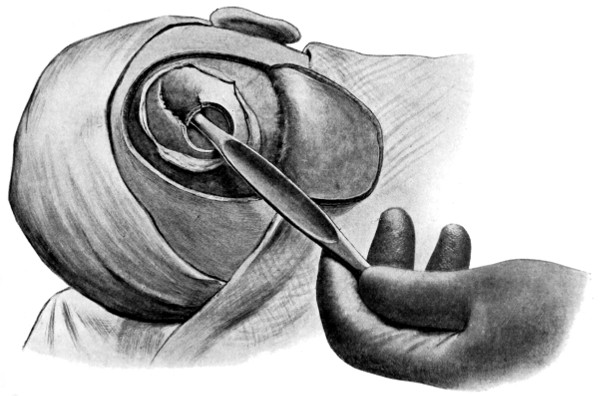

| 90. To illustrate the operations on the Gasserian ganglion | 317 |

| 91. To illustrate the operations for exposure of the Gasserian ganglion | 321 |